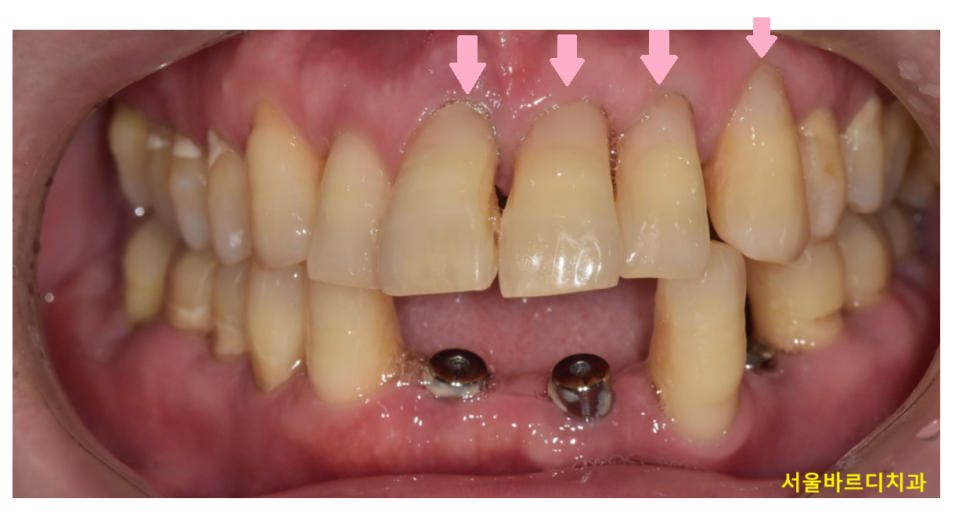

사진을 한번 봐볼까요~?

치아가 잇몸쪽 부위가 파여있죠~?

이런 증상을 우리는 치경부마모증이라고 부릅니다.

치아와 잇몸이 만나는 부분

치아의 목 부분이기 때문에 치경부라 말하는데요.

이 부위가 마모되어 치아가 깎여 나간 상태를 뜻합니다.

241224 치아 목 부위 = 치경부

230525 심하게 파인 치아